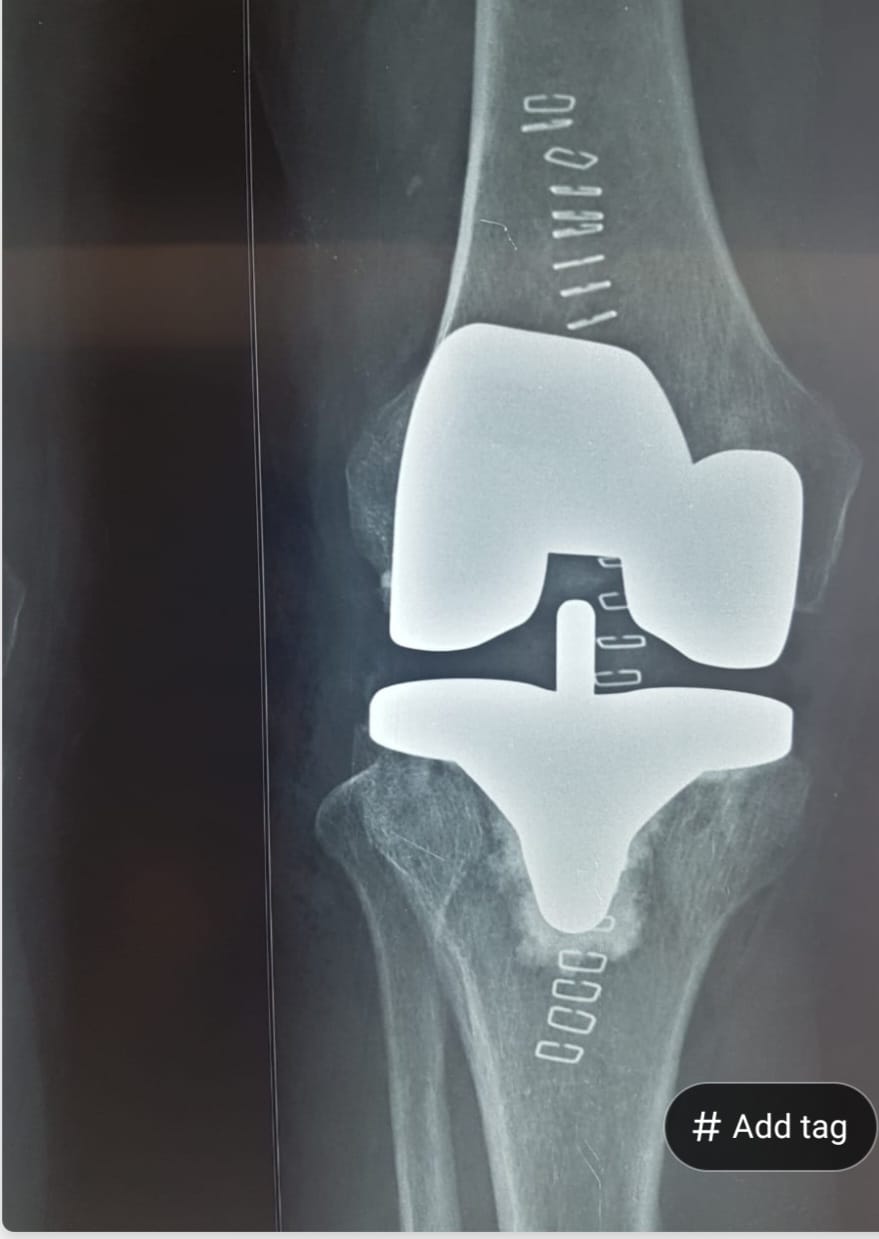

Knee Replacement Alternatives - 9 Non-Surgical Options To Try Before Surgery

Not ready for knee replacement surgery? Dr. Mayank Chauhan, orthopedic surgeon in Noida & Greater Noida, explains 9 proven non-surgical alternatives that can delay or sometimes avoid surgery altogether.